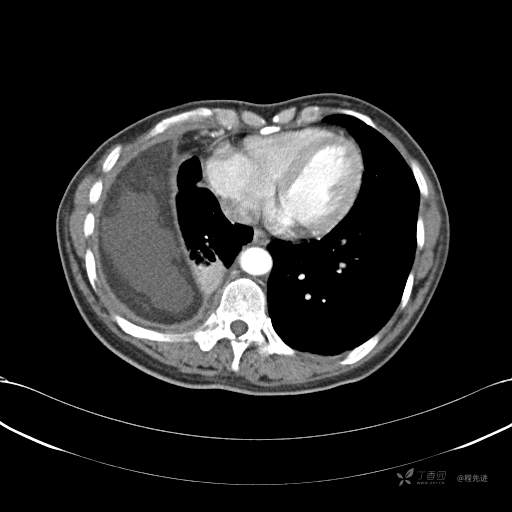

患者性别:女

患者年龄:51岁

简要病史:胸闷半年

肺淋巴管肌瘤病 (7)

乳糜胸 (8)